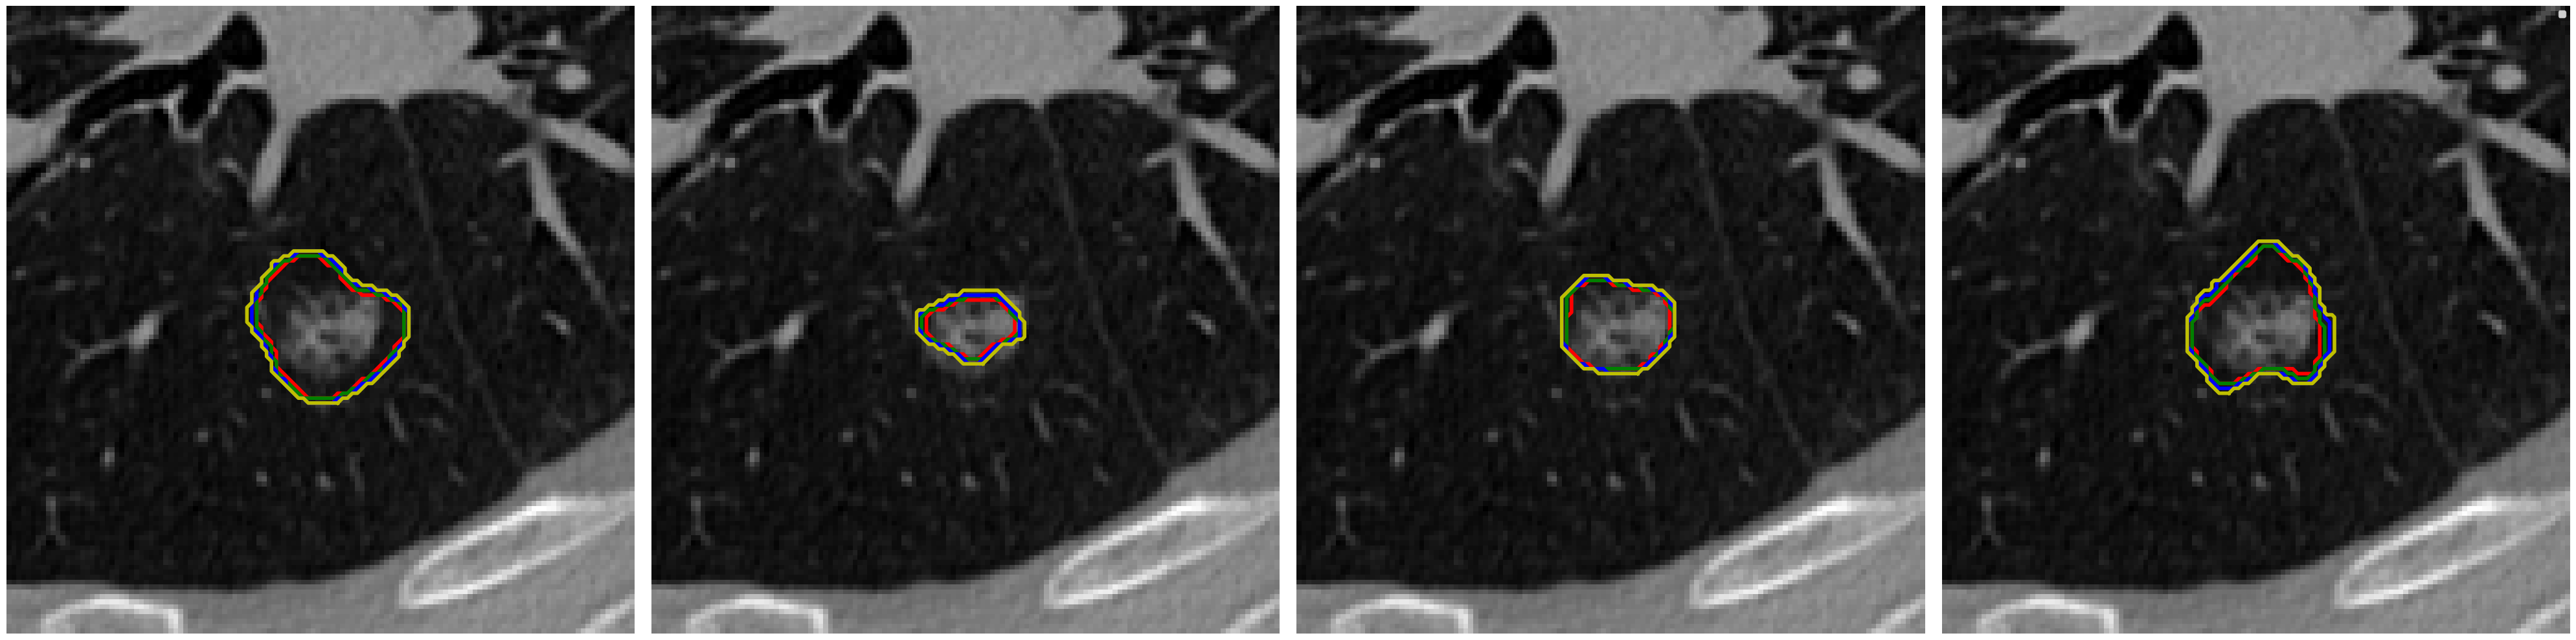

Visual comparison of segmentation results.

We provide visual comparisons of the segmentation results of all methods on the NPC dataset in Fig. 9 and Fig. 10, where different colors indicate the segmentation is obtained by different expert annotators. The segmentation results of ProSeg are more diverse and personalized than those of other methods. The segmentation results of ProSeg are more consistent with the ground truth while maintaining diversity among the generated segmentations. The results demonstrate that ProSeg effectively captures expert-specific characteristics and generates diverse segmentation results. For some methods, the segmentation from all the experts is the same, which means the diversity is poor. In Fig. 6(b), the second row shows the segmentation from our ProSeg, the third row shows the segmentation from the DPersona (stage 1) and the fourth row shows the segmentation from the DPersona (stage 2). For the second image, in the gold standard, three experts give segmentation containing two separate parts. Our ProSeg captures the character, while other models can hardly capture this difference, and generation methods can not tell which expert gives the two-part segmentation as shown in the figure that the color of the two-part segmentation is different from the Gold standard.